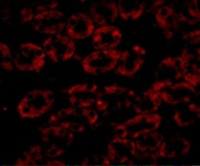

IHC-P analysis of human Ewing's sarcoma tissue using GTX34575 CD99 antibody [MIC2/1495R].